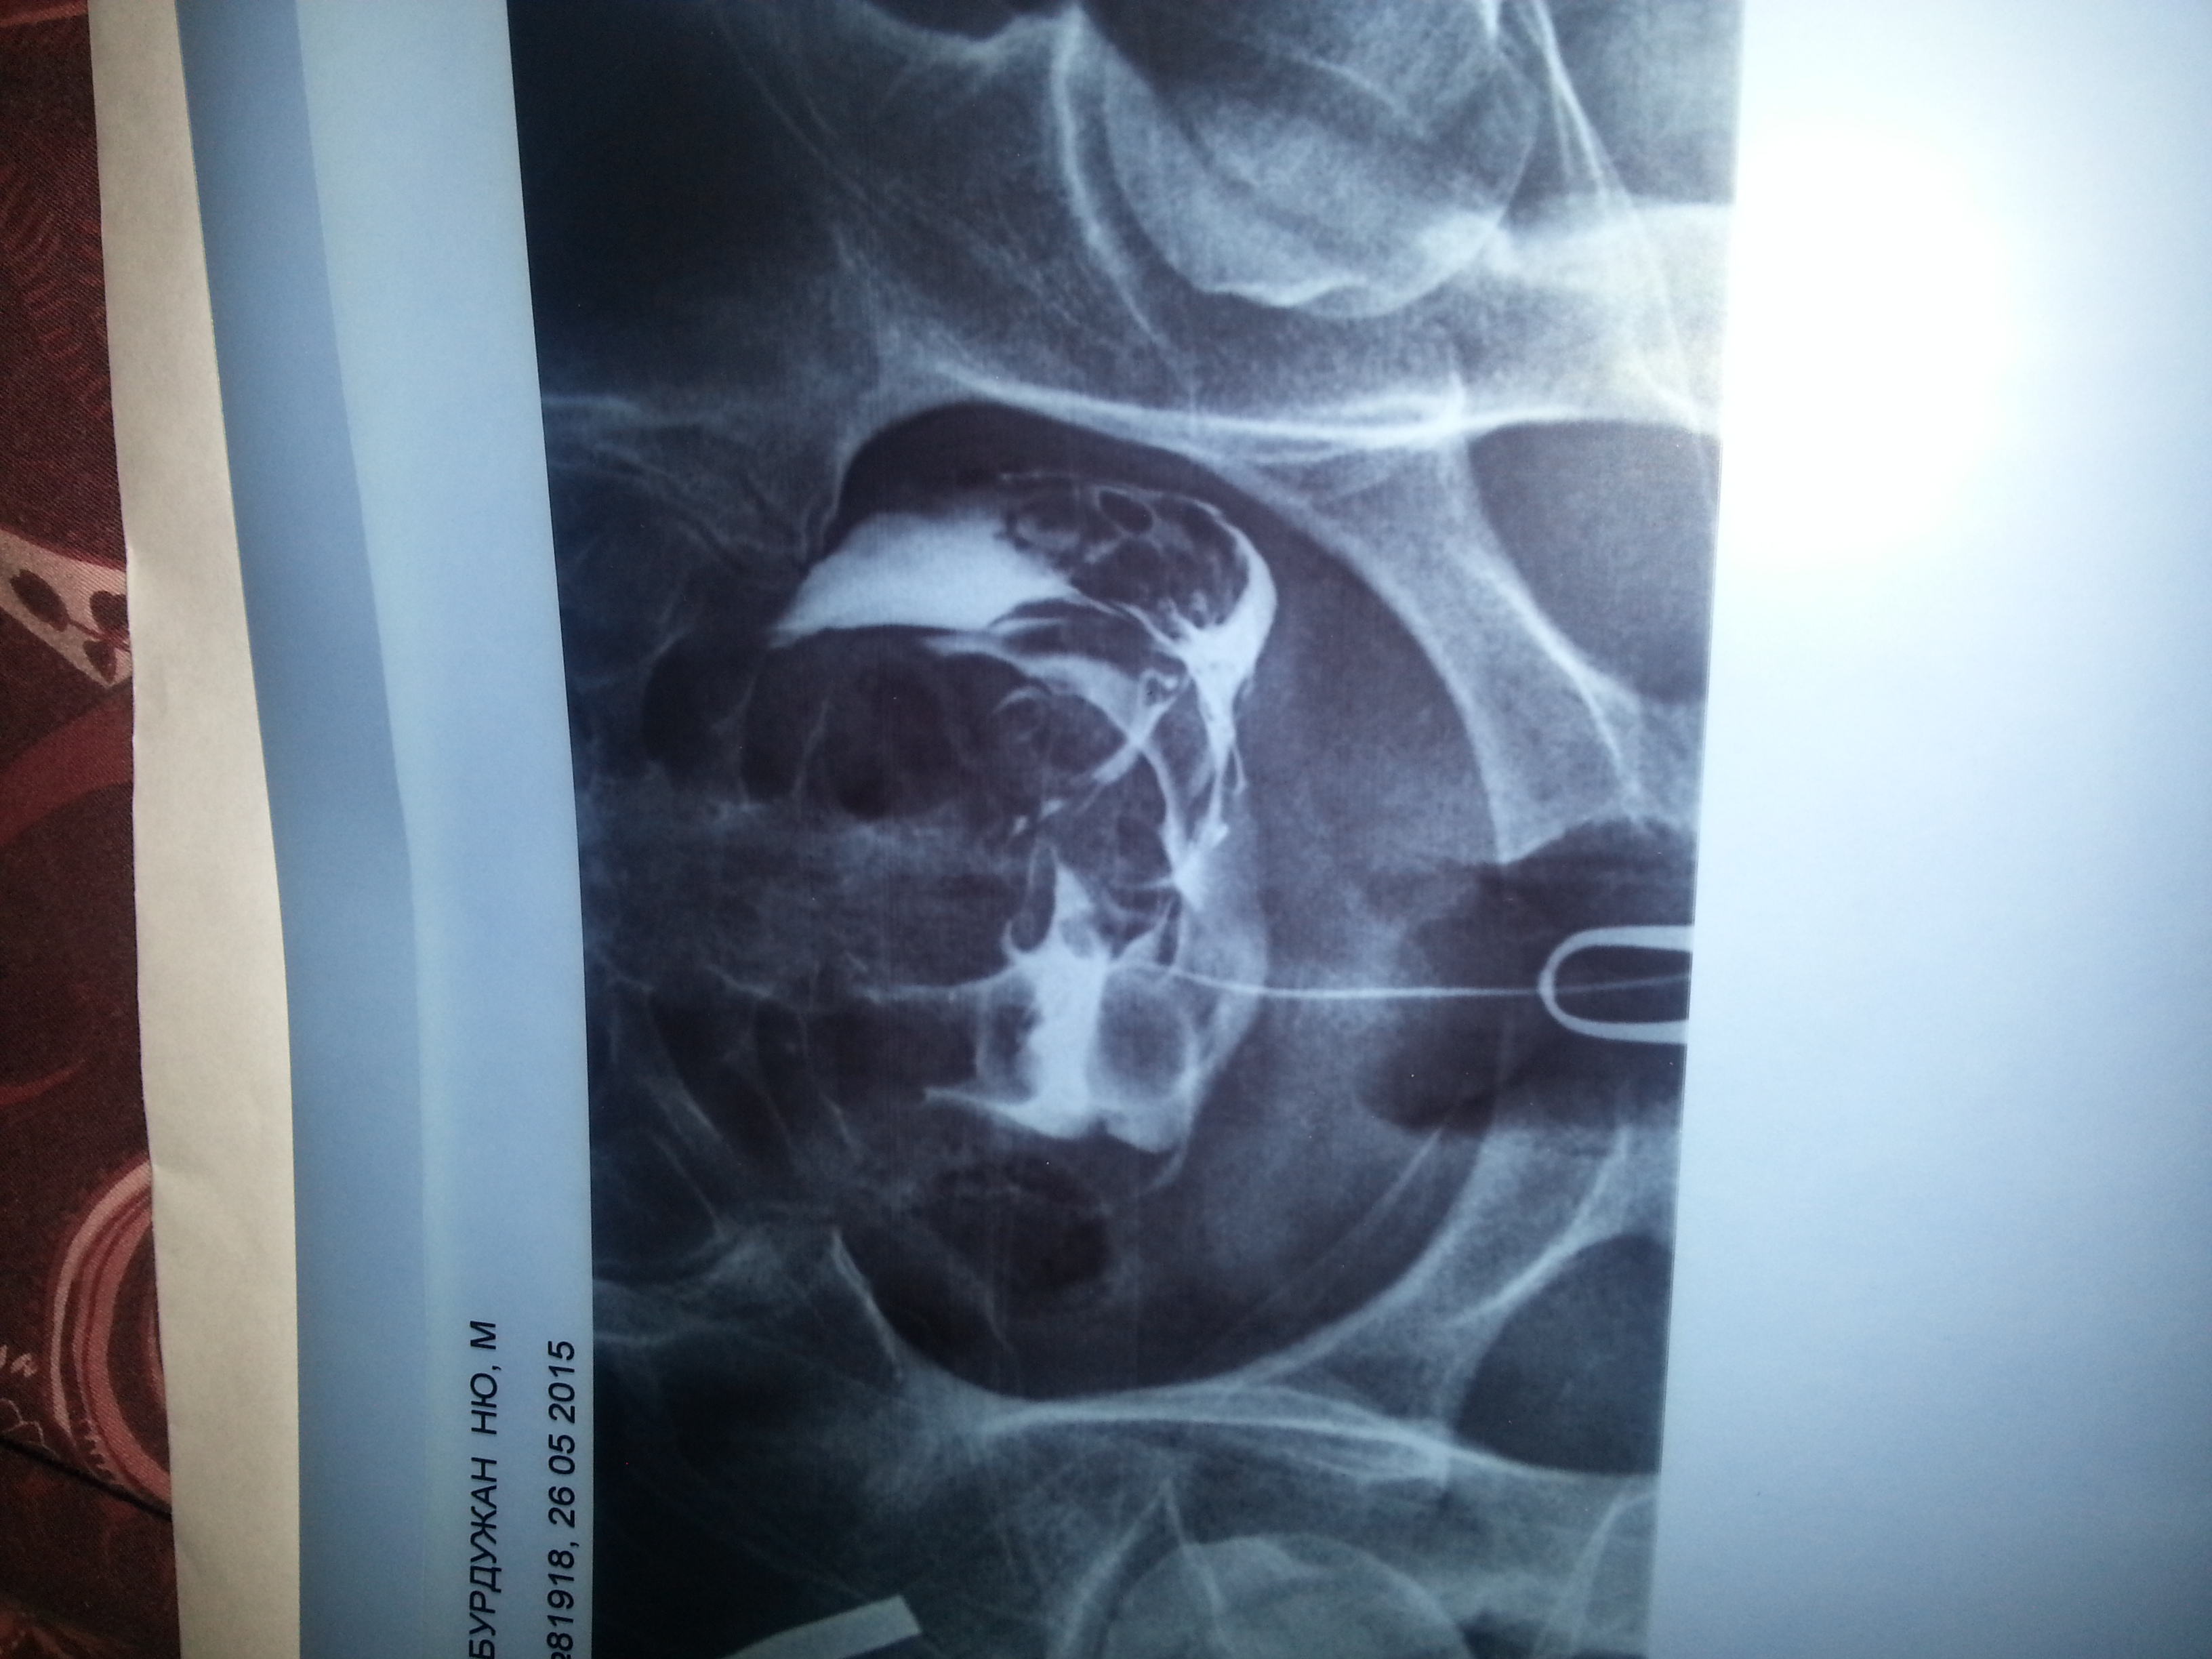

Медицинские снимки: Проходимость маточных труб